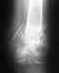

Добрый вечер! Случилось. Следующее: Был перелом голеностопа, врачи сказали что вывих связок, после чего неправильно сросся сустав, в результате опухоль на голеностопе и выкручивает стопу. Прибывали лечить укусами пчёл, но опухжоль не спадает. Быть может кто-то может помочь с лечением, какие способы возможны.благодарю

Без рентгенограмм невозможно уяснить, какое повреждение было, и и что имеется на сейчас. "Укусы пчел" - это не лечение ни при какой ситуации. Если есть деформация - устранить ее можно только хирургически. Что конкретно нужно делать - по смутному рассказу про неизвестно какой "перелом голеностопа" предложить невозможно. Можно показать снимки здесь, можно приехать на консультацию очно (Московская, 12, с собой паспорт, полис и все справки-снимки, относящиеся к делу).